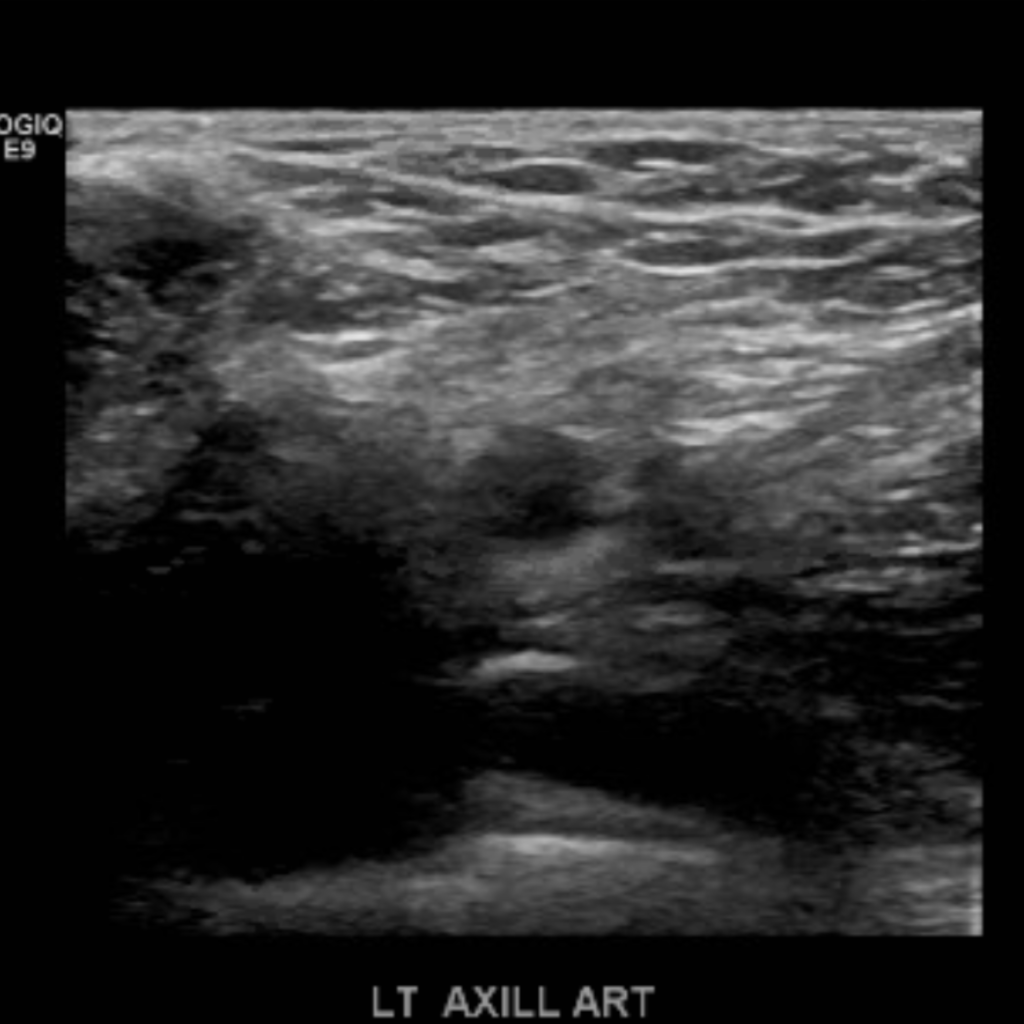

The subclavian artery arises from the brachiocephalic artery on the right and off of the aortic arch on the left. This artery further divides into the axillary, brachial, radial, ulnar, palmar and digital arteries respectively.